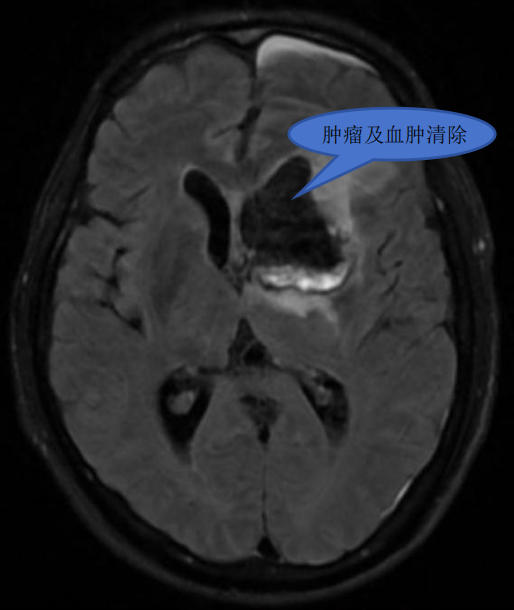

手术由王继斌副主任、罗绳祝主治医师、杨志医师,联合麻醉手术科团队共同完成。术中,王继斌副主任利用神经内镜的抵近观察优势在内镜下沿肿瘤边缘逐步、仔细的分离脑肿瘤,最终将肿瘤全切,同时清除颅内血肿。术后患者麻醉清醒、言语正常、四肢活动正常。

术后影像

术后病例标本检查提示:弥漫大B细胞淋巴瘤(非生发中心型)。